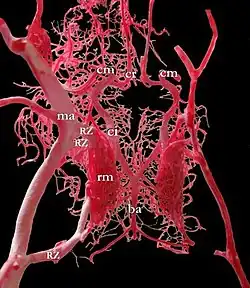

Blutversorgung des Gehirns

(Ansicht von unten, der rechte Schläfenlappen wurde teilweise entfernt)

Vier große Schlagadern versorgen das Gehirn des Menschen und der meisten Säugetiere mit sauerstoffreichem Blut (alte Bezeichnung: „arterielles Blut“). Je zwei liegen auf jeder Seite des Halses, vorn die inneren Halsschlagadern (Arteriae carotides internae) und hinten die Wirbelarterien (Arteriae vertebrales). Das Blut fließt nach der Passage des Gehirns über besondere venöse Hirnblutleiter (Sinus durae matris) ab, die gegenüber den Venen einige Besonderheiten aufweisen.